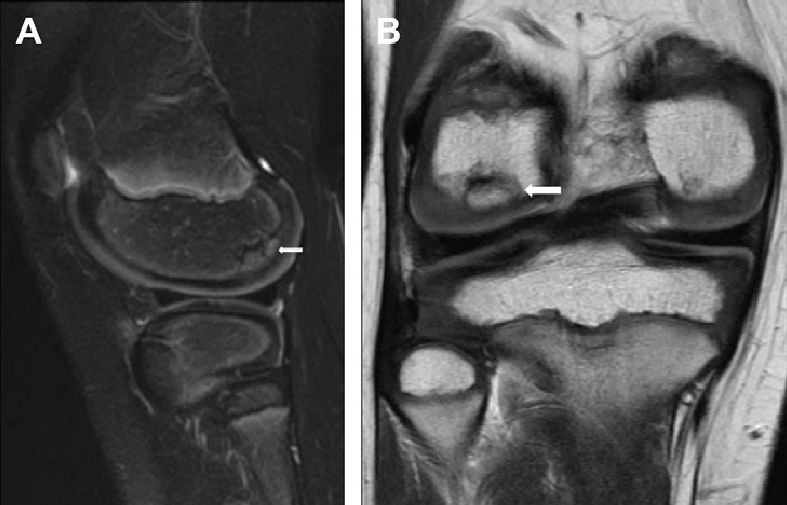

Osteochondritis dissecans (OCD) is a joint condition that occurs when a piece of bone and its overlying cartilage become loose due to a lack of blood supply. This can lead to pain, swelling, and potential joint instability, particularly in the knee. OCD commonly affects adolescents and young adults, often as a result of repetitive stress or minor trauma to the joint. Understanding the causes, symptoms, and treatment options for OCD is essential for managing the condition and preserving joint health.

OCD is a condition in which a portion of the bone beneath the cartilage in a joint loses its blood supply, leading to the separation of bone and cartilage. In some cases, the loose fragment may remain attached, while in others, it can break free and move within the joint, causing mechanical symptoms. OCD most commonly affects the knee, particularly the femoral condyles (the rounded ends of the thighbone), but it can also occur in other joints such as the elbow and ankle.

If the loose fragment moves within the joint, it can cause additional mechanical symptoms and discomfort.